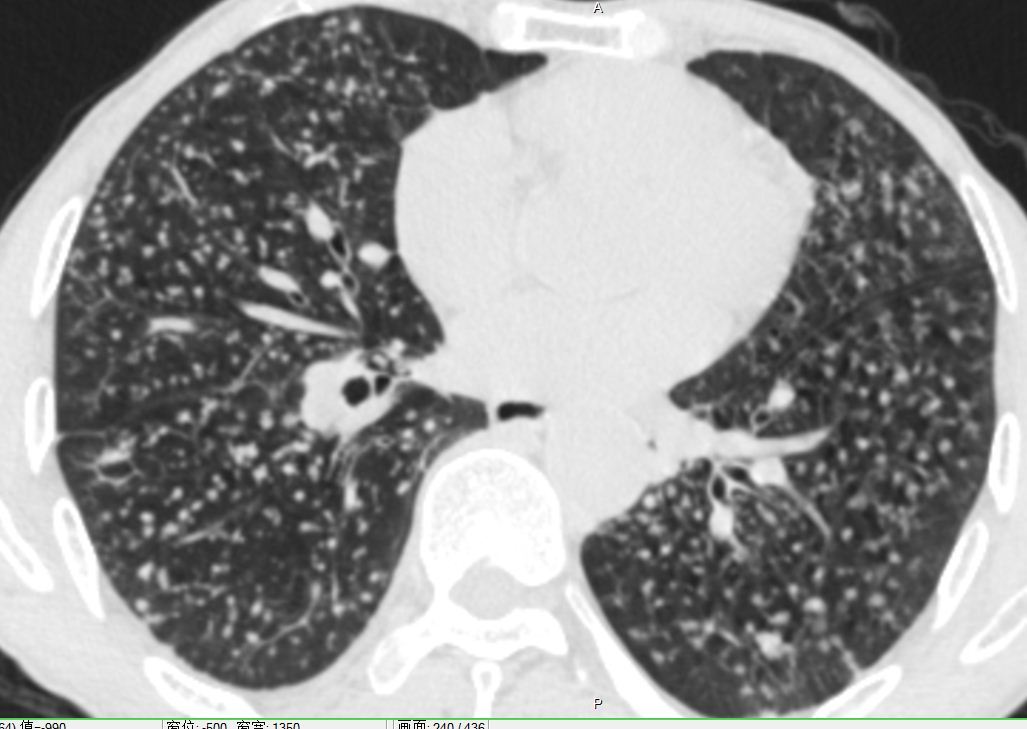

遇到尘肺莫慌张 (原创)_谢冬医生文章_上海市肺科医院-微医

图片尺寸1027x729